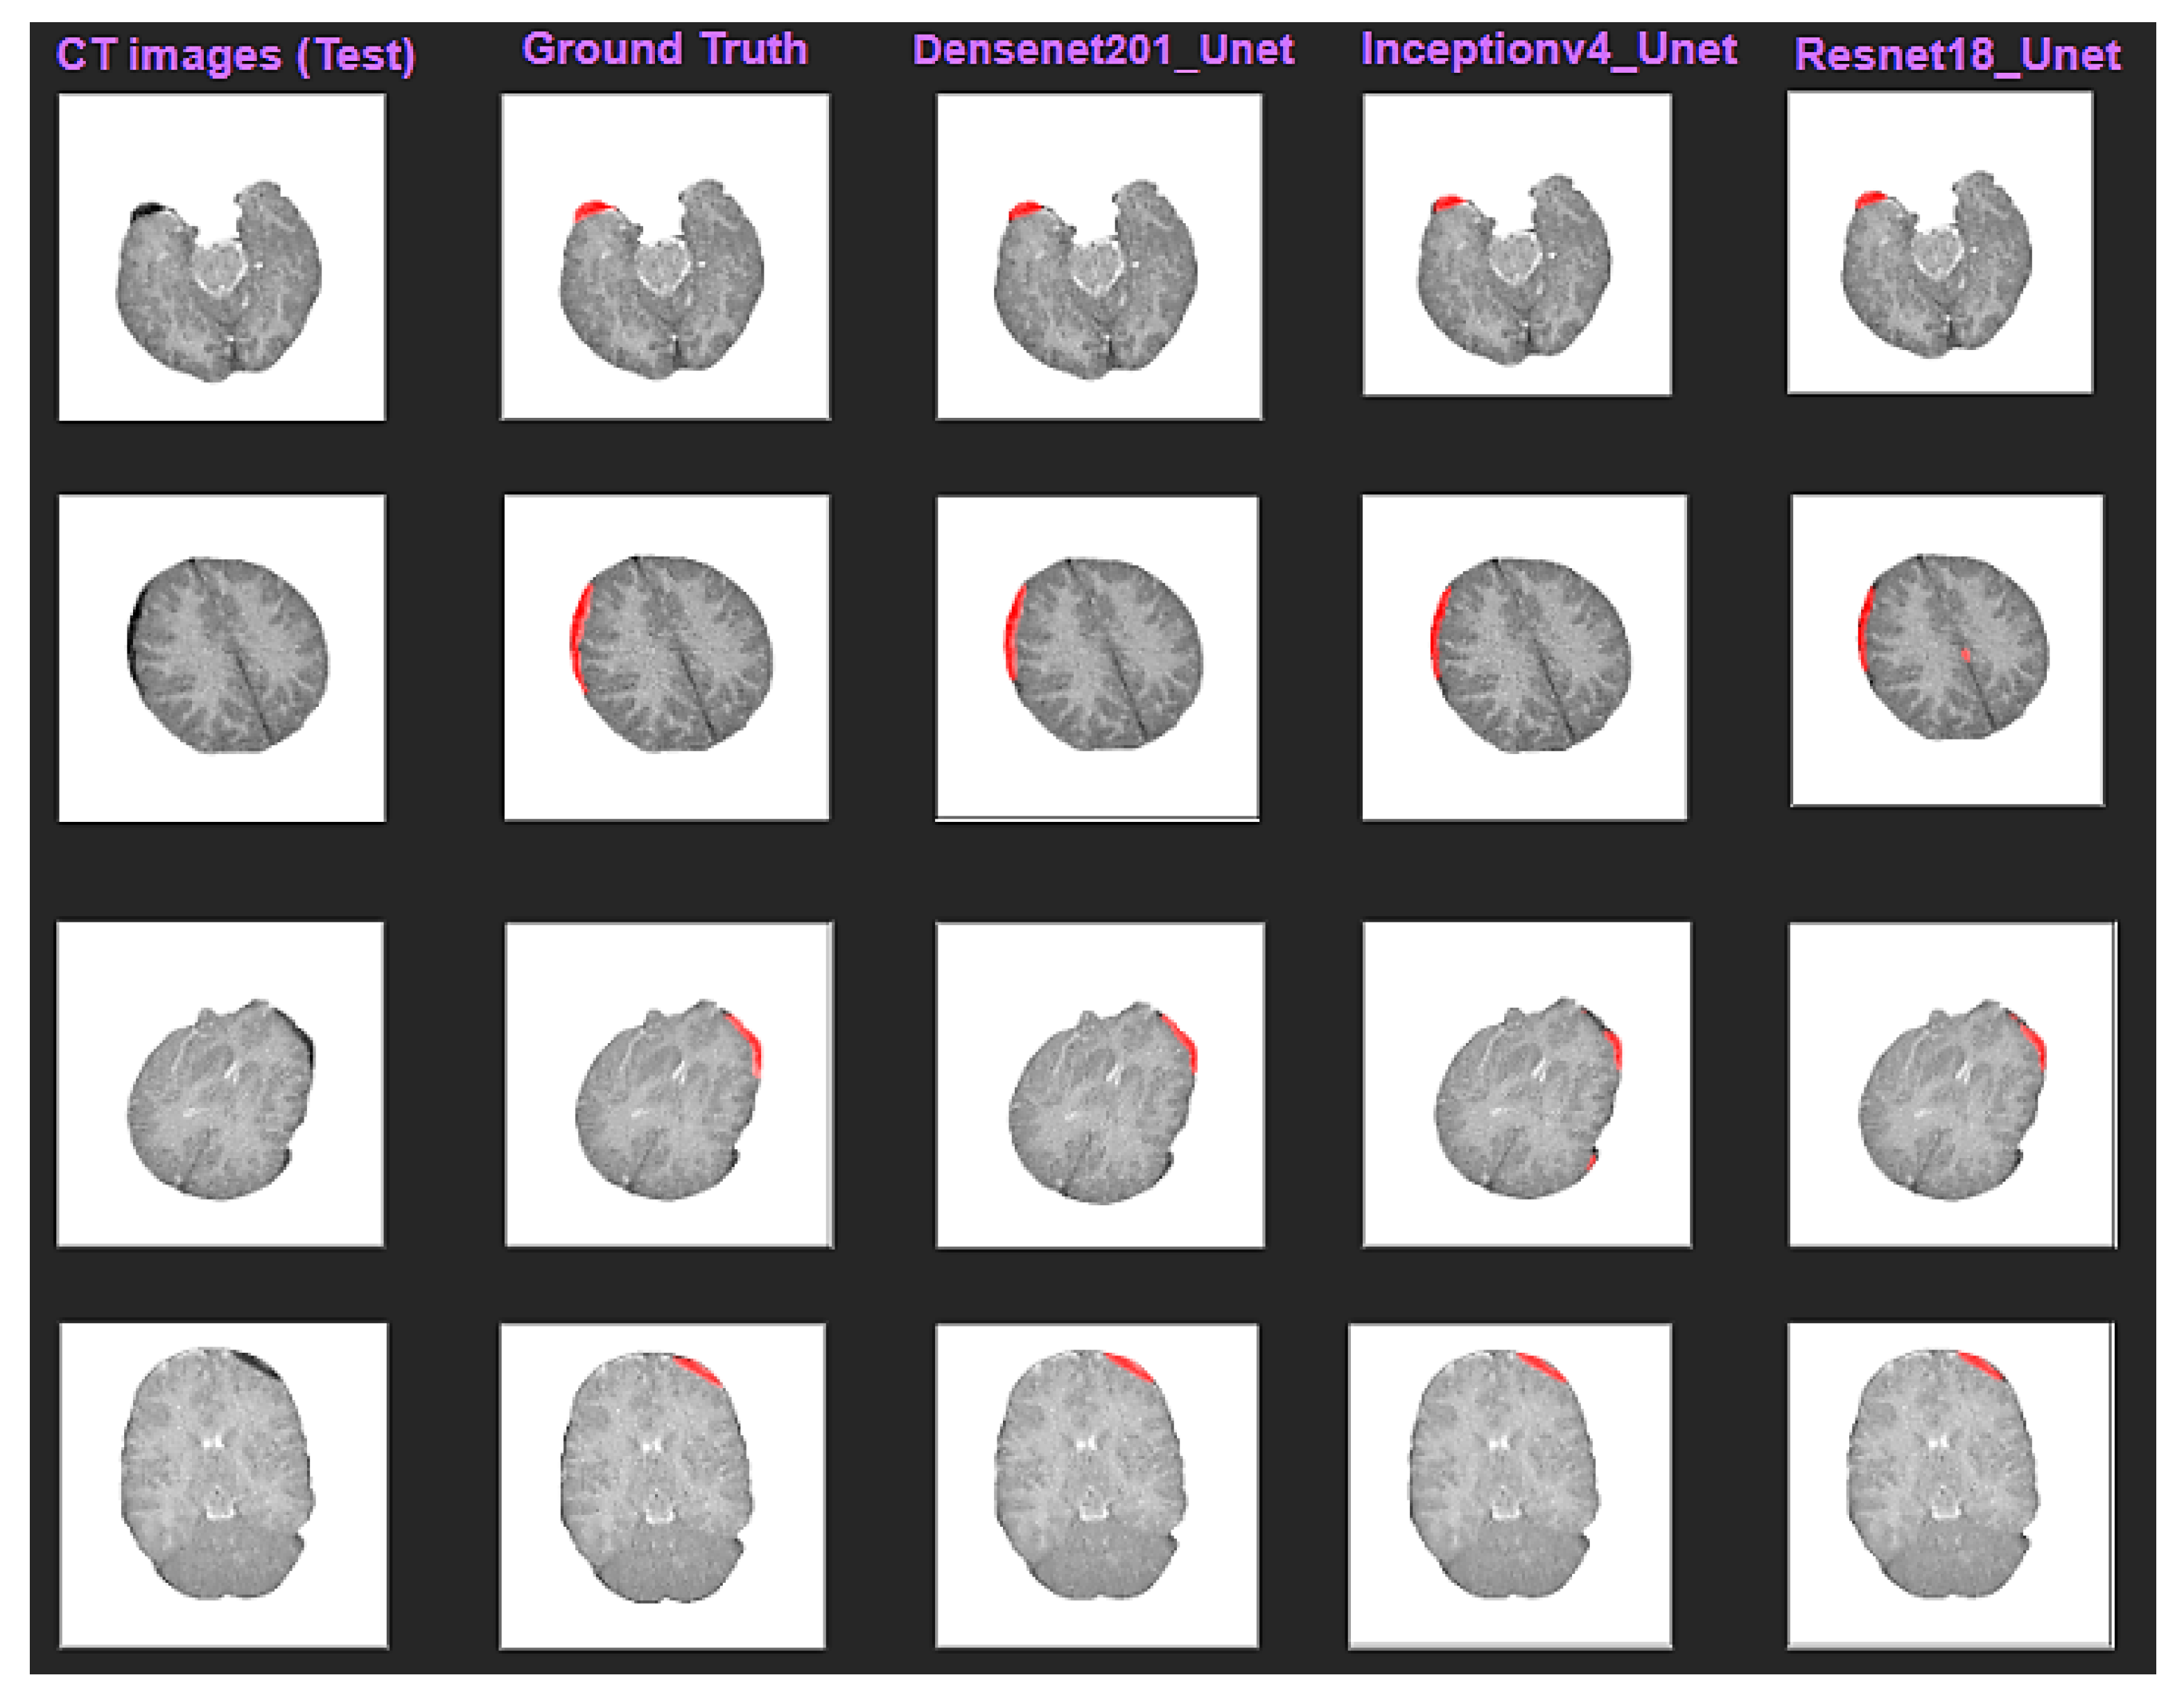

3.1. Intracranial Hemorrhage Segmentation

3.2. Reconstruction of 3D Models of ICH